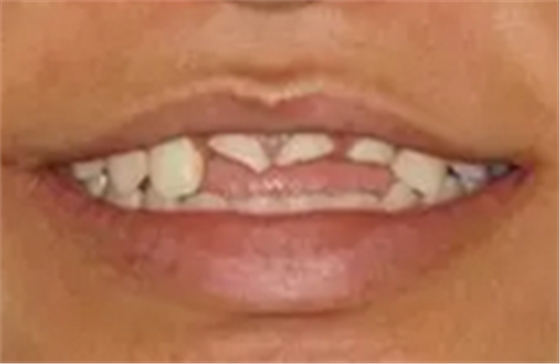

患者,女性,23岁,外伤导致上前牙折断3天。检查:中微笑 线;上颌右侧中切牙至左侧侧切牙残根,不松动,腭侧缺损达龈下5mm, 牙龈中等厚度,龈缘基本完好。CBCT显示:根长约11mm,牙根长轴与牙 槽突方向基本一致,唇侧骨板完好、厚度1.0mm,可用骨高度21mm。全身情况良好。

图1 术前微笑像